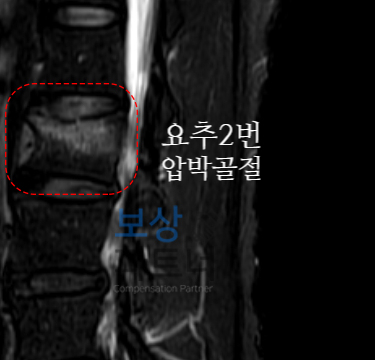

L2 부위의 골절 (요추2번 압박골절) X-ray 영상에서 L2(제2요추) 부위를 보시면, 정상적인 사각형 모양이 아닌 앞쪽이 눌려서 쐐기 모양으로 찌그러진 것이 보입니다. 마치 각설탕을 앞에서 눌렀을 때 주저앉는 모습과 비슷한데, 이것이 바로 압박골절입니다.

MRI에서도 같은 부위에 골절로 인한 부종과 손상이 뚜렷하게 확인되었습니다.

의뢰인의 모든 의무기록을 면밀히 검토하였습니다. 특히 영상 자료를 통해 압박률 27%, 후만각 16도가 명확히 확인되었는데요. 이는 약관상 **"약간의 기형 (15%)" **기준을 충족하는 명백한 장해 소견이었습니다.

이러한 내용이 담긴 **"후유장해 진단서" **를 공신력 있는 제3의료 기관에서 발급받았습니다. 팔꿈치의 운동제한 측정 결과, 약간의 장해 5%에 해당하셨는데요. 요추2번의 경우에는 압박율 27%, 후만각 12도로 측정되어 "척추의 뚜렷한 기형 (30%)"에 해당하였습니다. [상단의 이미지 참조]